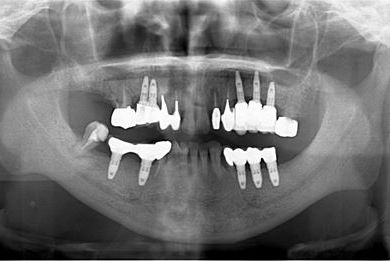

インプラントの症例写真 IMPLANT

骨再生インプラント治療

| 性別/年齢 | 男性 / 58歳 | ||||||||||||||||||||||||||||||||

| 主訴 | ブリッジがだめになったため、現在は部分入れ歯を使用しているが、インプラント治療を検討している。 | ||||||||||||||||||||||||||||||||

| 治療方針 | 左上奥の欠損部分をインプラント治療にて、機能的・審美的回復を行う。 | ||||||||||||||||||||||||||||||||

| 治療内容 | インプラント3本(GBR)、ハイブリッドセラミッククラウン3本 | ||||||||||||||||||||||||||||||||

| 総治療費 | 791,520円 | ||||||||||||||||||||||||||||||||

| 治療期間 | 10ヶ月 |